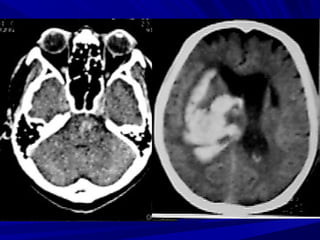

Glioblastoma

Maùu tuï trong

naõo vaø taêng